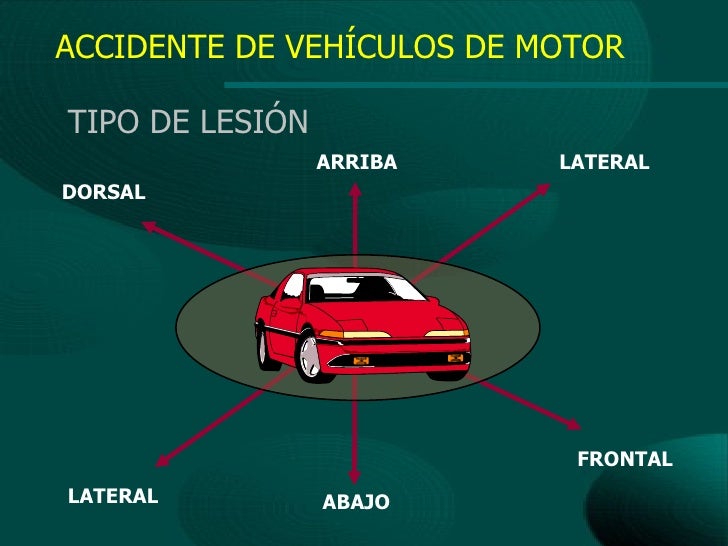

tipo de lesión

dorsal

arriba

lateral

el choque ocurre contra un costado del vehículo

lateral

abajo

frotal